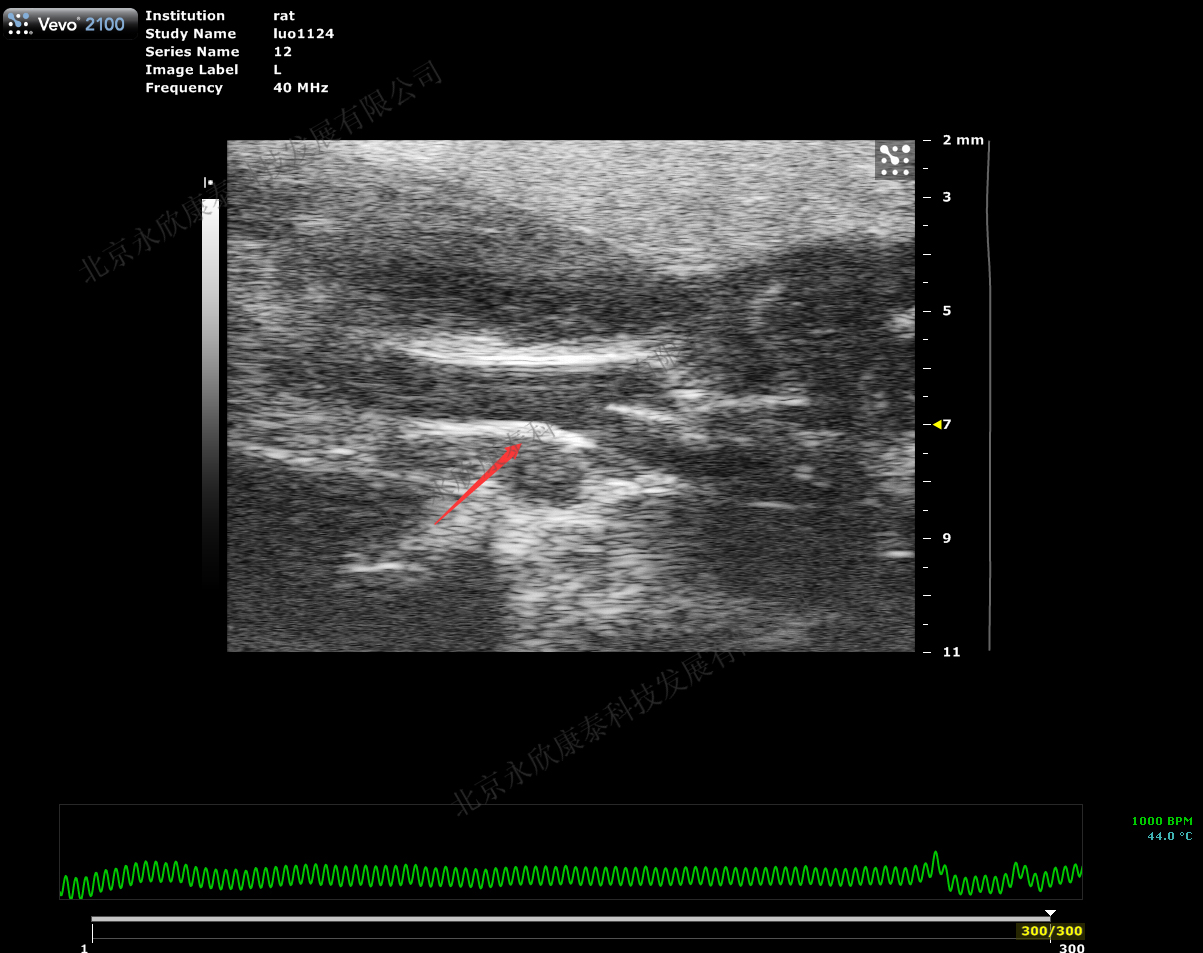

2、超声评价斑块程度

文献和实验记录仪并在在同一时间内完成睡眠日记。研究人员会量化参与者的个人睡眠时长、睡眠持续时间和入睡时间来评估睡眠规律性,通过评估参与者的冠状动脉钙化(Coronary artery calcium, CAC)、颈动脉斑块、颈动脉中膜厚度(Carotid intima-media thickness, cIMT)和踝肱指数(Ankle brachial index,ABI)等亚临床动脉粥样硬化相关指标(图 2),使用 COX 回归模型计算现患比(Prevalence ratio,PR)等数值,得出两者之间